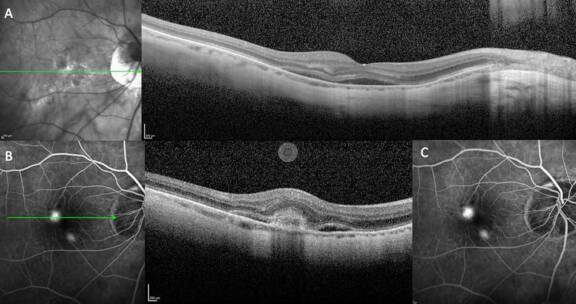

Figures 1A et 1B. L’OCT chez un patient myope fort de l’œil droit (A) et gauche (B) montre une segmentation difficile, rendant l’analyse de la couche des fibres nerveuses rétiniennes (RNFL) non fiable pour le diagnostic et le suivi du glaucome chez ce patient.